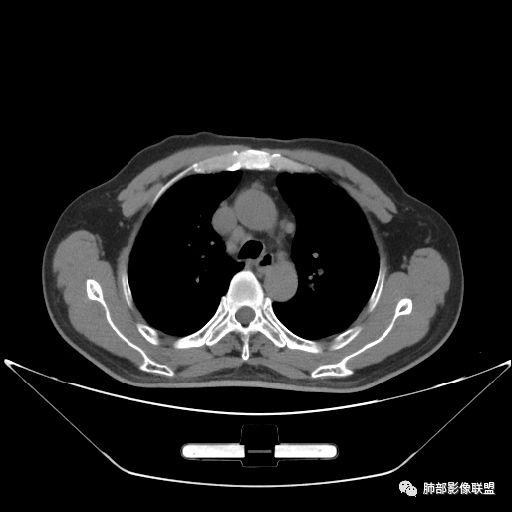

住院4天后行胸部增强CT

静脉期

老年男性,因“咳嗽咳痰1月余。”入院。病程中咳嗽咳痰,咳黄白痰,间断咯少许鲜红色痰血。PPD阳性。胸CT:右肺中叶外侧段支气管管腔阻塞,大片实性病变,病灶边缘光滑,部分边缘膨隆,可见分叶,肺门及纵隔可见肿大淋巴结,并可见钙化。增强可见病灶明显强化,而且延迟强化明显,病灶内多发低密度区,内见血管影,血管变细、部分血管破坏。考虑恶性病变可能性大,鉴别慢性肉芽肿性病变。

胸CT:跨叶大肿块,主体在中叶,右中叶外侧段支气管阻塞,病灶部分边缘膨隆,可见分叶,部分边缘平直,肺门及纵隔可见肿大淋巴结。增强病灶不均匀强化,延迟强化明显,病灶内多发低密度区,内见血管飘浮,部分血管变细、模糊。考虑:恶性病变可能性大,大细胞?淋巴瘤?鉴别慢性肉芽肿性病变。

右肺中叶软组织肿块,外围向内生长,叶间胸膜向前内移位,肿块近肺门侧跨叶,中叶外侧段支气管截断,密度不均匀,双侧肺门及隆突下见肿大淋巴结,增强后呈中度不均质强化,肺动脉供血,多发坏死区,边界尚清,坏死区域内见结构,结合病史考虑恶性,鉴别诊断1结核,爬行征是沿支气管树分布,外宽,内窄,周围有卫星灶,内气管狭窄后扩张,此例沿叶间胸膜长轴分布,气管有截断,不典型。2炎性肉芽肿,符合的地方下方层面增强后延迟性轻度环形强化,不符临床无发热等急性感染病史,实验室指标不符,病灶周围渗出及慢性炎性改变有,不明显。

吴婧老师和南边老师都对该病例进行了深入分析。从支气管管壁的增厚,支气管狭窄后扩张,支气管粘液栓,病灶形态,到病灶不均匀强化及坏死彻底,到周边病灶及肺组织空气的潴留,加之纵隔内淋巴结肿大伴钙化等等,都支持慢性炎性病灶,尤其是结核。

墨西哥仙人掌征---结核        影像上结核灶,粗大的均匀枝干,推测是支气管囊状扩张引起的,在非支气管区,形成圆形坏死囊群;如果这些坏死比较稀薄,又遇到扩张支气管,就会形成粗大的“墨西哥仙人掌”。结核引起的支气管近端炎症纤维化,可以造成支气管阻塞,从而将干酪样坏死物封堵在管腔内。仙人掌主干内部应该是干酪为主,稀薄的,具有流动性,时间久了会出现钙化。